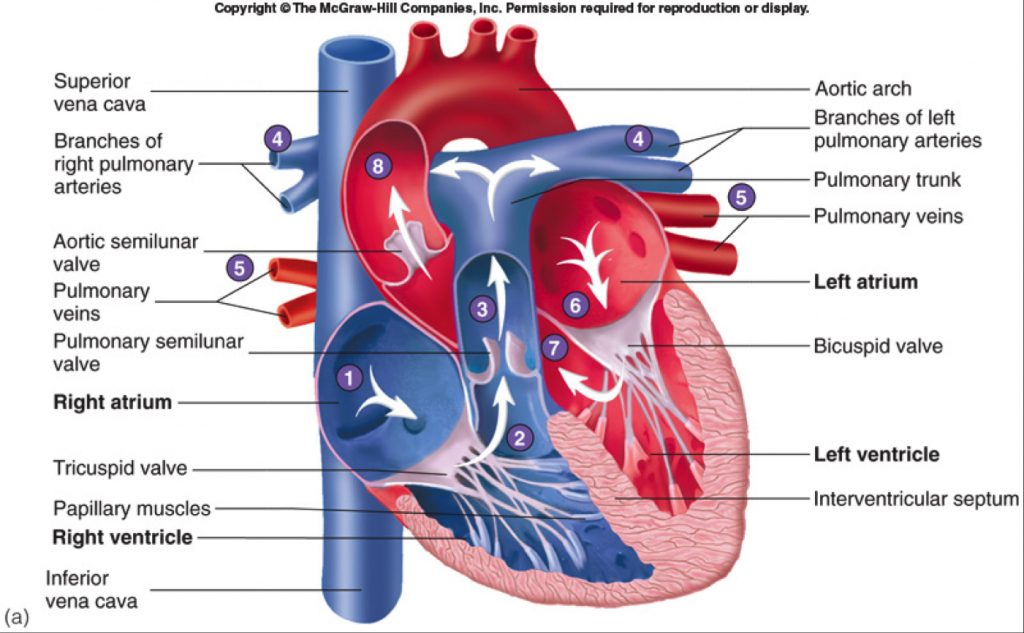

What are the parts that make up a human heart? Diagrams and More | Human heart diagram, Heart

What are the parts that make up a human heart? Diagrams and More | Human heart diagram, Heart  Human heart by kortney16 on DeviantArt

Human heart by kortney16 on DeviantArt  Human Heart-Gross structure and Anatomy - Online Biology Notes

Collection of Human heart clipart | Free download best Human heart clipart on ClipArtMag.com  15 Diagram Of Heart In Human Body | Robhosking Diagram

Human Heart Diagram Without Labels - koibana.info | Human heart diagram, Heart diagram, Human  Human Heart Diagrams | 101 Diagrams

Human Heart Diagrams | 101 Diagrams  Human Heart Simple Drawing at GetDrawings | Free download

human body heat loss (With images) | Human heart diagram, Human anatomy picture, Human heart anatomy  42+ How To Draw Simple Heart Diagram Gif | World of Images

Anatomy of the Heart: Physiology | Health Life Media  Human Heart Anatomy Drawing at GetDrawings | Free download

Human Heart - Circulatory System | OER Commons  de Location Of Human Heart In Body mar webmds heart anatomy page provides a detailed image of

Anatomy of the human heart  Human Heart Drawing Line Work stock vector art 481404348 | iStock